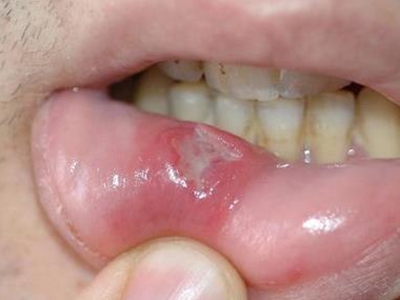

白塞病首发症状多为口腔溃疡,单发或多发,圆形或不规则形,边界清楚,有自愈倾向,但会反复发作。